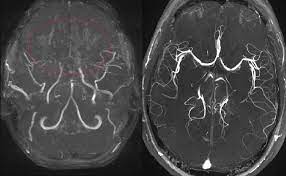

3. 신경영상검사(Neuroimaging): 뇌의 혈관 상태를 평가하기 위해 다양한 신경영상 검사가 사용됩니다. 주로 사용되는 검사에는 다음이 포함됩니다:

- CT 스캔(Computed Tomography): CT 스캔을 통해 뇌 혈관의 형태와 혈류를 시각화할 수 있습니다.

- MRI(Magnetic Resonance Imaging): MRI를 사용하여 뇌혈관을 자세하게 평가하고 혈류 문제를 확인할 수 있습니다.

- 혈관조영술(Cerebral Angiography): 혈관조영술은 혈관 내부 구조를 자세하게 시각화하기 위해 사용됩니다. 이 절차는 모야모야병을 진단하는 가장 확실한 방법 중 하나입니다.